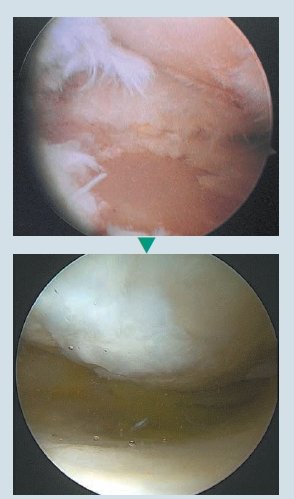

무릎연골 결손이 매우 심했던 환자가 수술 1년이 지난 후, 새롭게 연골이 생성돼 무릎상태가 건강하게 됐다. 관절내시경 영상.

무릎연골 결손이 매우 심했던 환자가 수술 1년이 지난 후, 새롭게 연골이 생성돼 무릎상태가 건강하게 됐다. 관절내시경 영상.

무릎연골 결손이 매우 심했던 환자가 수술 1년이 지난 후, 새롭게 연골이 생성돼 무릎상태가 건강하게 됐다. 관절내시경 영상.

무릎연골 결손이 매우 심했던 환자가 수술 1년이 지난 후, 새롭게 연골이 생성돼 무릎상태가 건강하게 됐다. 관절내시경 영상.퇴행성 관절염, 초기에는 약물치료